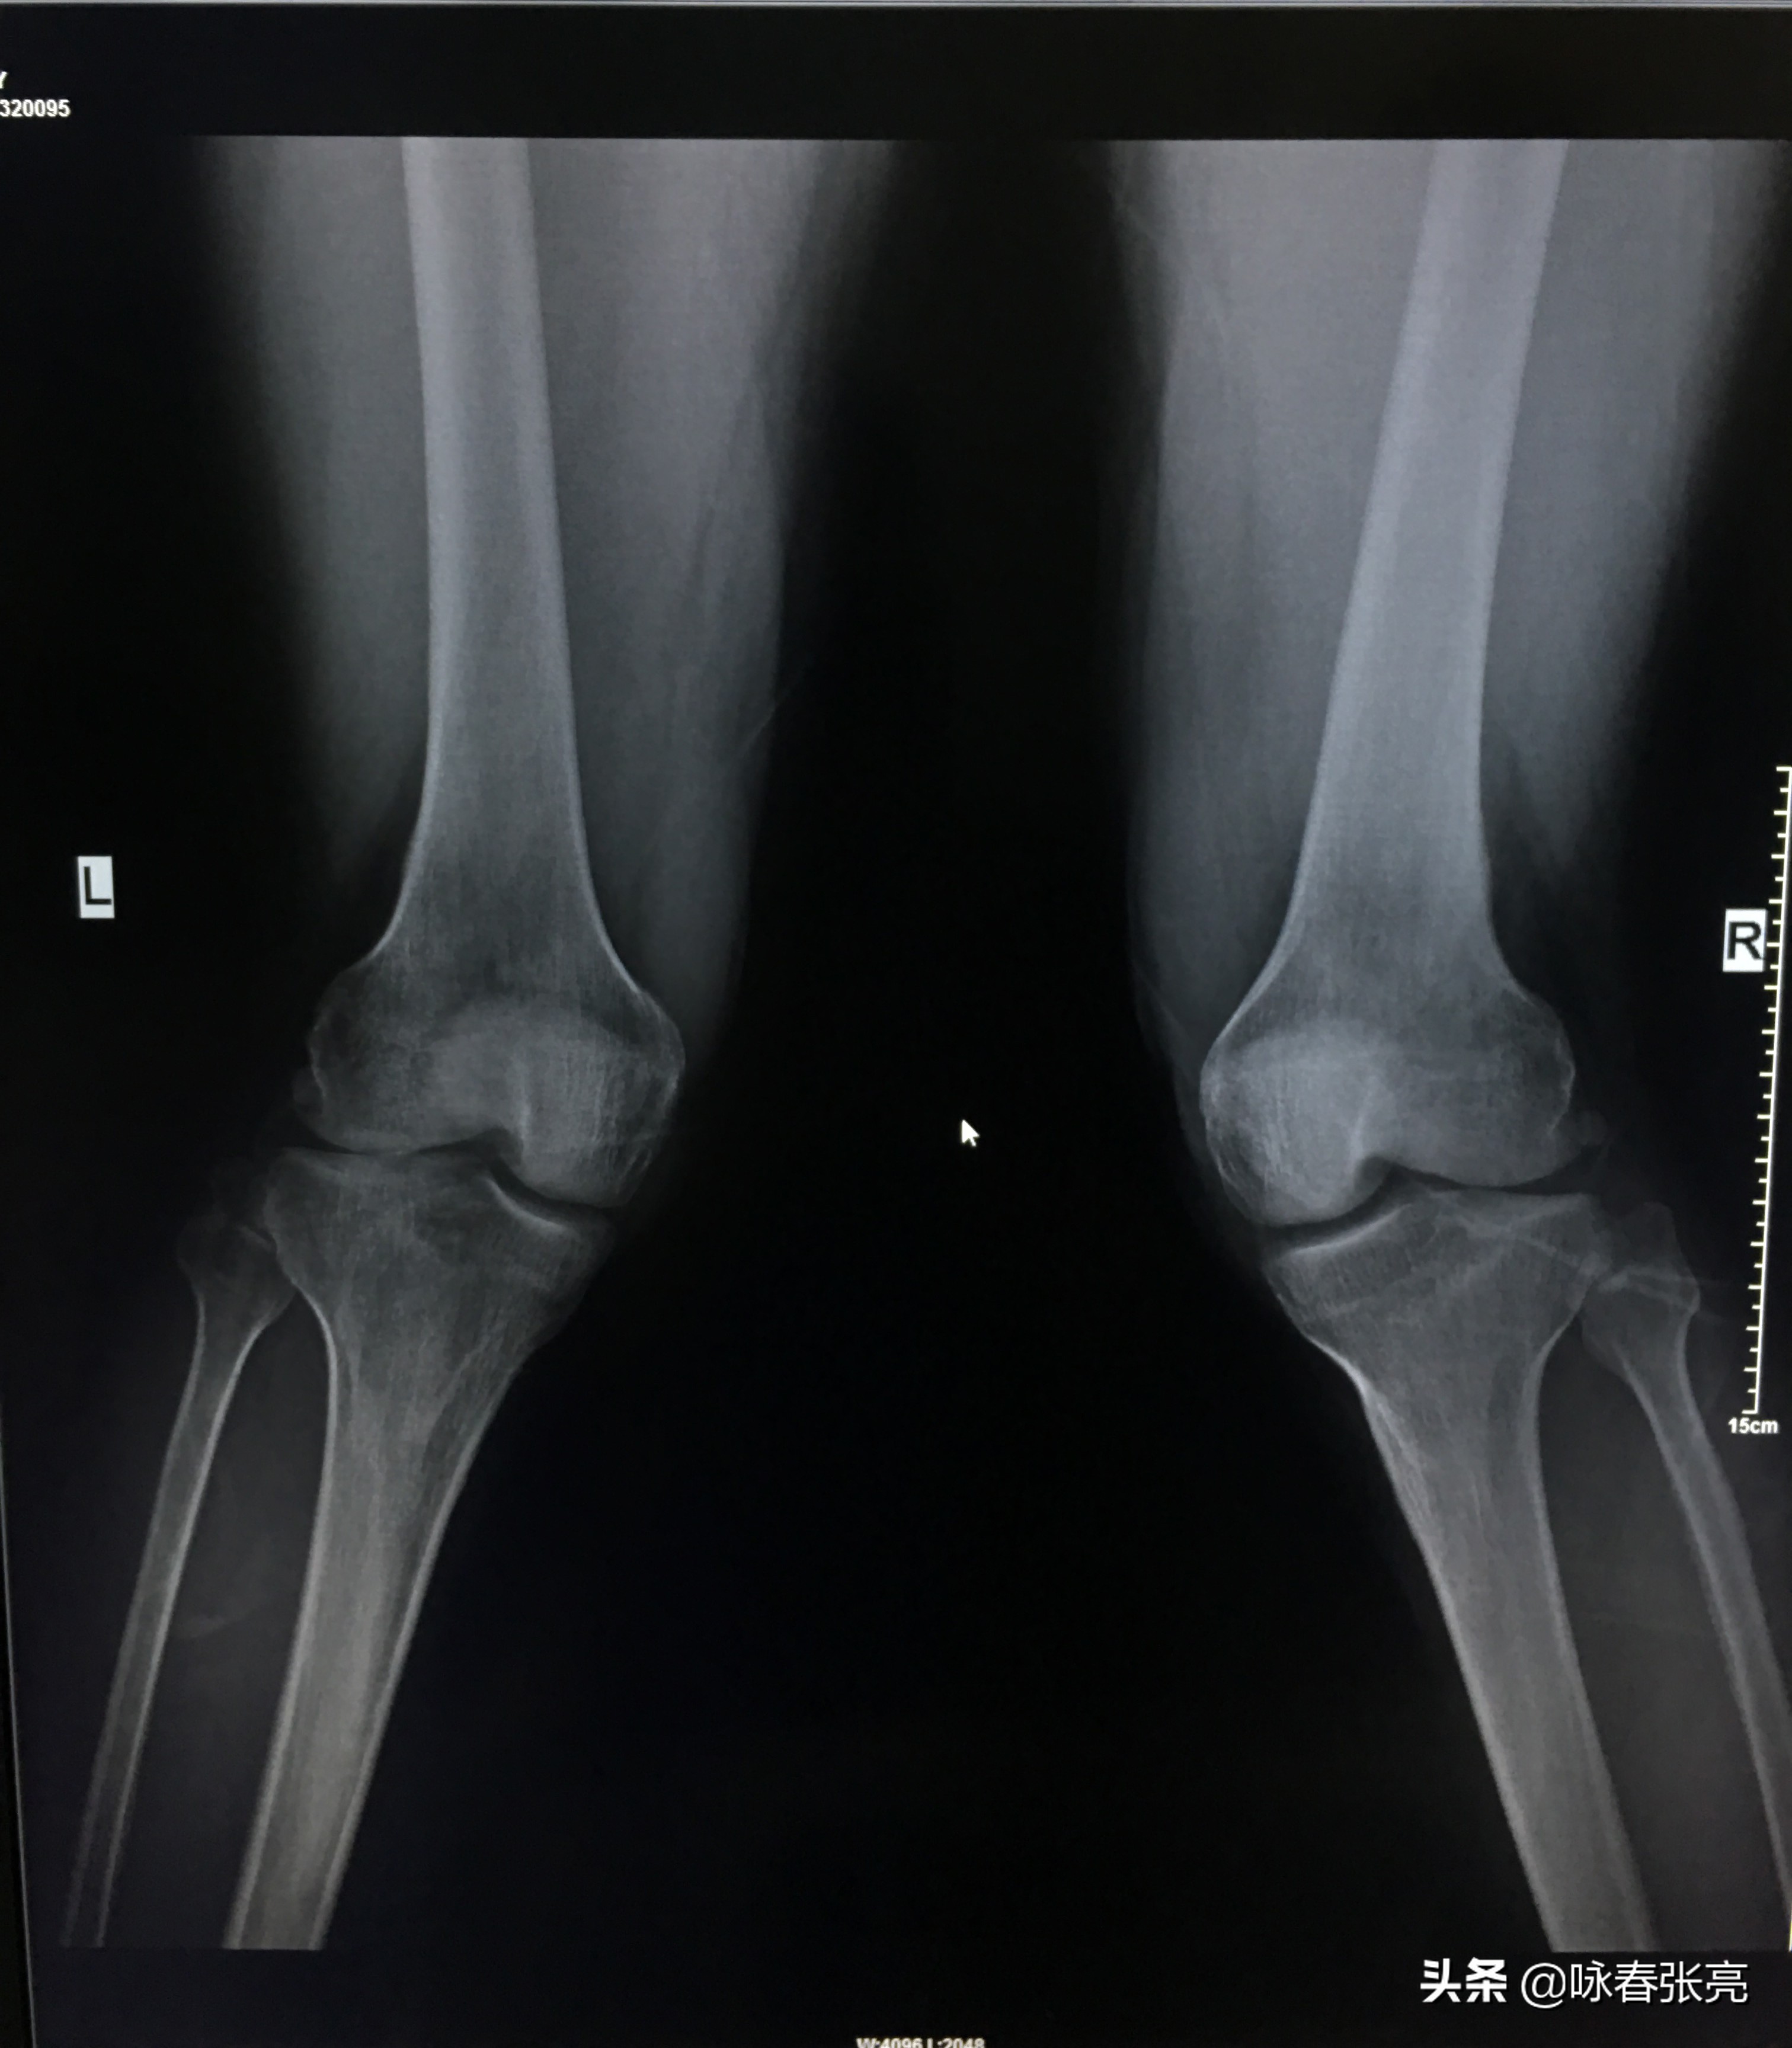

膝关节正面观

拳架有高、中、低之分。咏春拳是以高姿马步站立,这种马步是咏春拳所特有的,咏春拳的”马“有“钳羊马“和”二字钳 羊马”。依据《人体解剖学》理论,膝关节能绕冠状轴和垂直轴做屈伸、旋转和回旋运动.绕冠状轴屈伸是膝关节最主要的功能,正常的范围是 - 10〬~135〬。当膝关节屈曲时,半月板受力时扇形角增大,半月板的受力就越不均匀;膝盖前面半月板的受力减小,厚度增加;而膝盖后面半月板的受力则大幅度增加,厚度明显减薄,因此,半月板的变形会大大增加,从而造成膝关节损伤。而咏春拳扎马或坐马,膝不过足尖,这样,使膝关节绕冠状轴屈伸不超过135〬。客观上保护了膝关节免于受损。